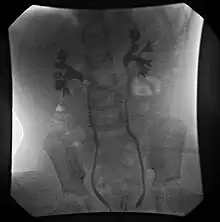

| Ultrasound image showing abnormal vesicoureteral junction and dilated distal ureter resulting in primary vesicoureteral reflux. | |